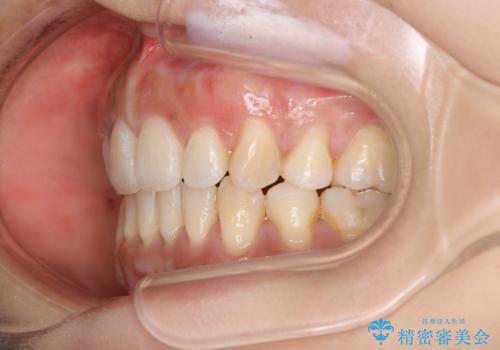

出っ歯で口が閉じずらい ワイヤー抜歯矯正

- 出っ歯がきになるとのことで来院されました。

上顎の前歯は前方に傾斜しており、下あごの前歯にもガタガタがありました。

上下左右の小臼歯を合計4本抜歯して矯正することとしました。